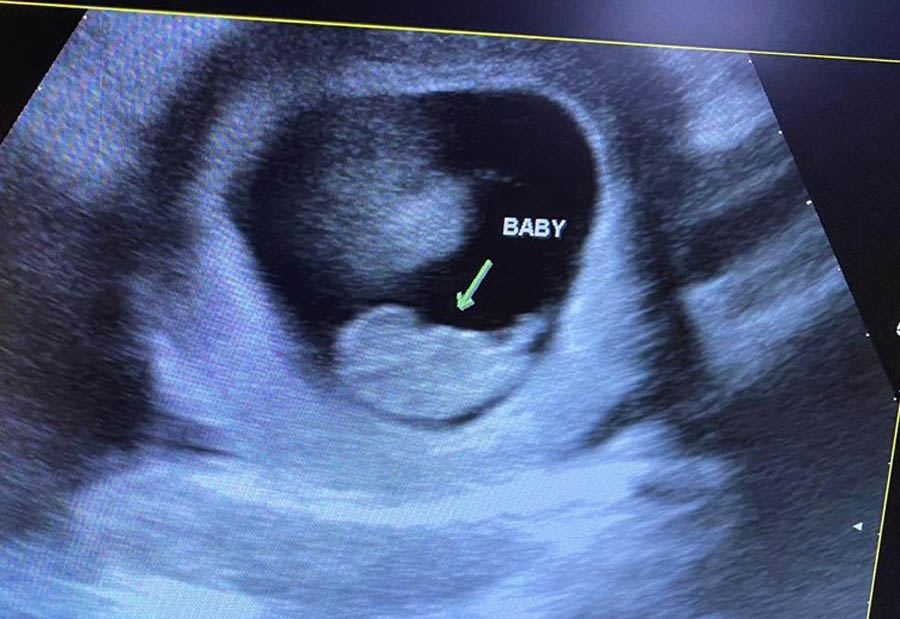

Leo overcomes abortion pill—see that baby roar!